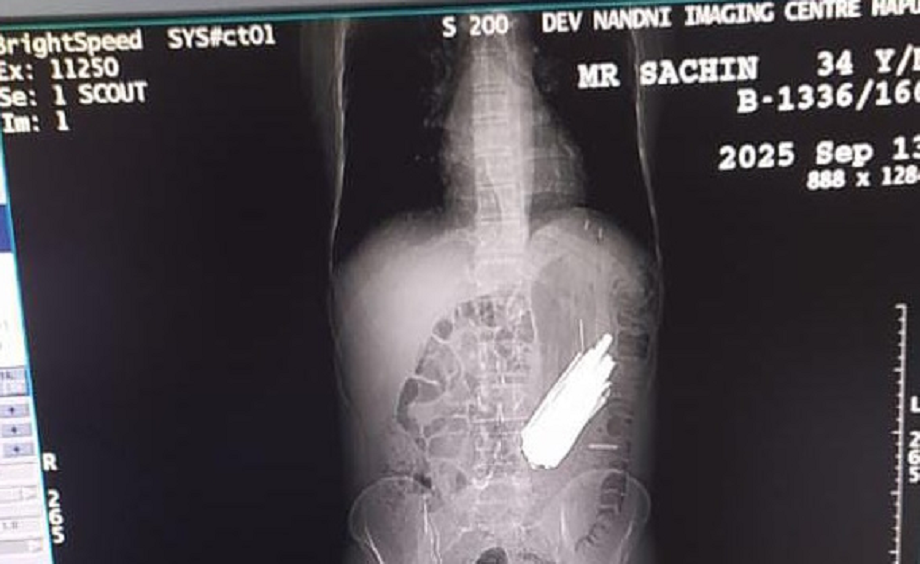

In a shocking incident in Hapur district, 29 spoons, 19 toothbrushes, and two pens were removed from the stomach of Sachin, a 40-year-old drug addict, during surgery. Sachin, a resident of Bulandshahr, was admitted to a drug de-addiction center where he swallowed the items after experiencing stomach pain. An ultrasound and X-ray revealed the incident.

Shortly thereafter, he experienced abdominal pain and worsened health, and received treatment. Doctors discovered the contents after performing an abdominal ultrasound and X-ray. The contents were removed after a four-hour operation at a private hospital in the city.